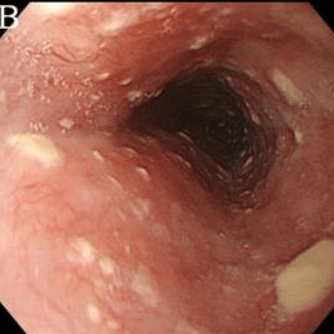

Эндоскопическая классификация кандидозного эзофагита по Kodsi

Степень IV: Те же изменения, что и при III степени, плюс контактная кровоточивость слизистой оболочки и иногда сужение просвета пищевода